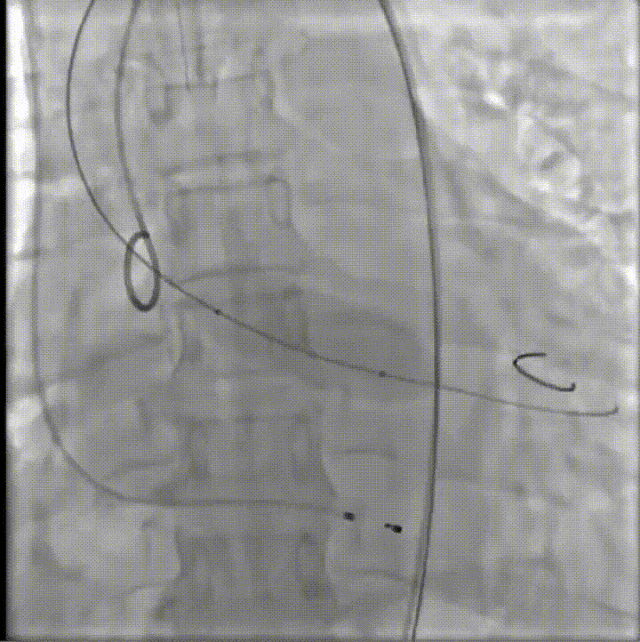

患者病史 体检发现心脏瓣膜病半月余,平素无症状 ,有高血压病史。 后来院复查诊断为:主动脉瓣狭窄(重度)、先天性主动脉瓣二叶瓣畸形、心室肥厚、升主动脉扩张心功能 I 级(NYHA 分级)、高血压病 2 级(极高危)。 术前 CT:Type0型二叶瓣,瓣叶增厚,无钙化,类风湿性;瓣环径25.6mm,LVOT稍收窄,瓣环水平夹角66.6°,轻微横位心;左右冠开口高度可,瓣叶不长,无冠脉风险;心室收缩末内径约32mm,室壁增厚;外周入路无明显迂曲,无钙化、双侧内径可、双股中分叉,右侧为主入路能够支持20F大鞘通过。 造影角度及入路:LAO 6° CAU 13° 手术策略 采用右侧股动脉为主入路,左侧为辅助入路,常规穿刺。推荐使用20球囊预扩,预装TAV29瓣膜,初始定位对齐瓣环上0mm开始释放。 手术过程 20号球囊预扩无明显腰征 输送器过弓跨瓣顺滑 80%工作位观察 术后造影,瓣膜释放位置良好,无瓣周漏 术后超声:人工生物瓣释放后形态满意,瓣叶开放、关闭活动良好,无瓣周漏;跨瓣血流速度降至 2.5m/s,平均压力梯度6mmHg,符合手术预期。 Prostyle A®预装干瓣——“刚柔并济”助力临床最优化解决方案: 丝滑过弓能力:Prostyle A®短瓣架设计联合远端超滑亲水涂层,即使没有联合使用snare,都可以柔顺过弓,该例横位心的患者更好的展现了输送系统的柔顺性; 平衡的径向支撑力:该例患者Type0型二叶瓣,术后形态展开良好且无瓣周漏,在横位心等复杂情况下实现稳定锚定。 80%可回收设计:80%工作位观察,起搏时间更短,对患者损伤减少到最小,也利于术中精准调整瓣膜位置,保证术后效果。

患者病史 男性,74y, 因 “发现心脏瓣膜病 1 年,加重伴喘气半年” 入院。门诊检查显示主动脉瓣重度AS并伴轻-中度AR。患者基础疾病较多:胸腹主动脉多发穿透性溃疡、心功能III级等,手术指征明确,但风险极高。 术前CT LVOT- Annulus 倒梯形,对植入瓣膜有挤压位移风险,Annulus直径23.7mm,瓣叶增厚,钙化集中在无冠窦边缘。 左冠脉开口高度可,瓣叶不长、窦部空间较大,无冠脉风险;室间隔膜部较短,有一定PPI风险,心脏角度37.9°;心室较小,有一定循环崩溃风险,术前注意补液。 术前造影角度及入路:血管入路散在钙化、无迂曲;主动脉弓条件好、双侧股动脉直径大、右股穿刺点侧壁存在环形钙化 左右重合位:RAO 7° CAU 21° 右窦中心位:LAO2 1° CAU 1° 手术策略 20mm球囊预扩后植入AV26瓣膜,同时做好预防循环崩溃、传导阻滞的应急预案。 术中挑战 1)球囊预扩:20mm球囊预扩时无明显 “腰征”,但存在少量反流,提示瓣膜钙化与解剖结构对扩张的阻力不均 2)首次释放偏差:第一次定位释放时,瓣膜在 “开花” 过程中下滑约 3mm,工作位观察显示小弯侧瓣周漏较多(深度超过完全覆膜区),需二次调整。 3)二次精准定位:以猪尾导管为参照,将定位点调整至 “猪尾 - 2mm” 处,结合真实窦底深度(较深)重新释放,最终瓣膜位置稳定,瓣周漏显著减少。 术后即刻效果: 瓣膜形态良好,跨瓣压差从术前的 67mmHg 降至 6mmHg,且无明显瓣周漏,冠脉开口通畅; Commisural Alignment 术后即刻超声: Prostyle A®预装干瓣——助力临床最优化解决方案: √ 平衡的径向支撑力:特殊的解剖结构下位置形态良好,术后跨瓣压差大幅降低,血流动力学改善明显; √ 80%可回收设计:支持术中二次调整释放位置,保证精准释放; √ 平衡的收腰设计&Commissural Alignment设计: 为患者后期冠脉PCI保留了生命通道;